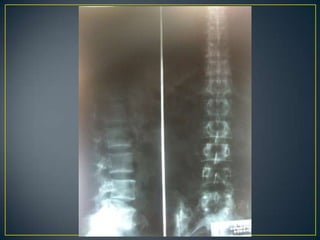

60% de las Fx del tarso2% de todas las fracturas87% Hombres de 40 añosLesiones asociadas: 30-50%M. inf. Contralateral 5%M. infhomolateral 25%Columna vertebral 10%Fx abiertas 5%

PADECIMIENTO ACTUALInicia el lunes 28 de febrero del 2011 en la tarde, al estar pintando su casa, sufre caída de aproximadamente 8 metros de altura, sin alteraciones de la conciencia, cayendo parado y recibiendo impacto en ambos pies, posteriormente cursa con dolor en ambos calcáneos e incapacidad para deambular, es llevado al servicio de urgencias del IMSS en Altamira donde no puede ser completa su valoración debido a la falta de rayos X, se decide su traslado al IMSS HGR 6 donde es recibido en el servicio de urgencias a las 23:00 horas, se realiza una rx lateral de ambos pies, es diagnosticado por traumatología como fractura multifragmentada de ambos calcáneos, sin lesiones en columna vertebral o cadera, se estable como tratamiento cirugía, se ingresa para su internamiento, sube a piso el 01-03-11 a las 11:45 horas y después se realiza TC la cual confirma el diagnostico antes dado

60% de lasFx del tarso2% de todas las fracturas87% Hombres de 40 añosLesiones asociadas: 30-50%M. inf. Contralateral 5%M. infhomolateral 25%Columna vertebral 10%Fx abiertas 5%